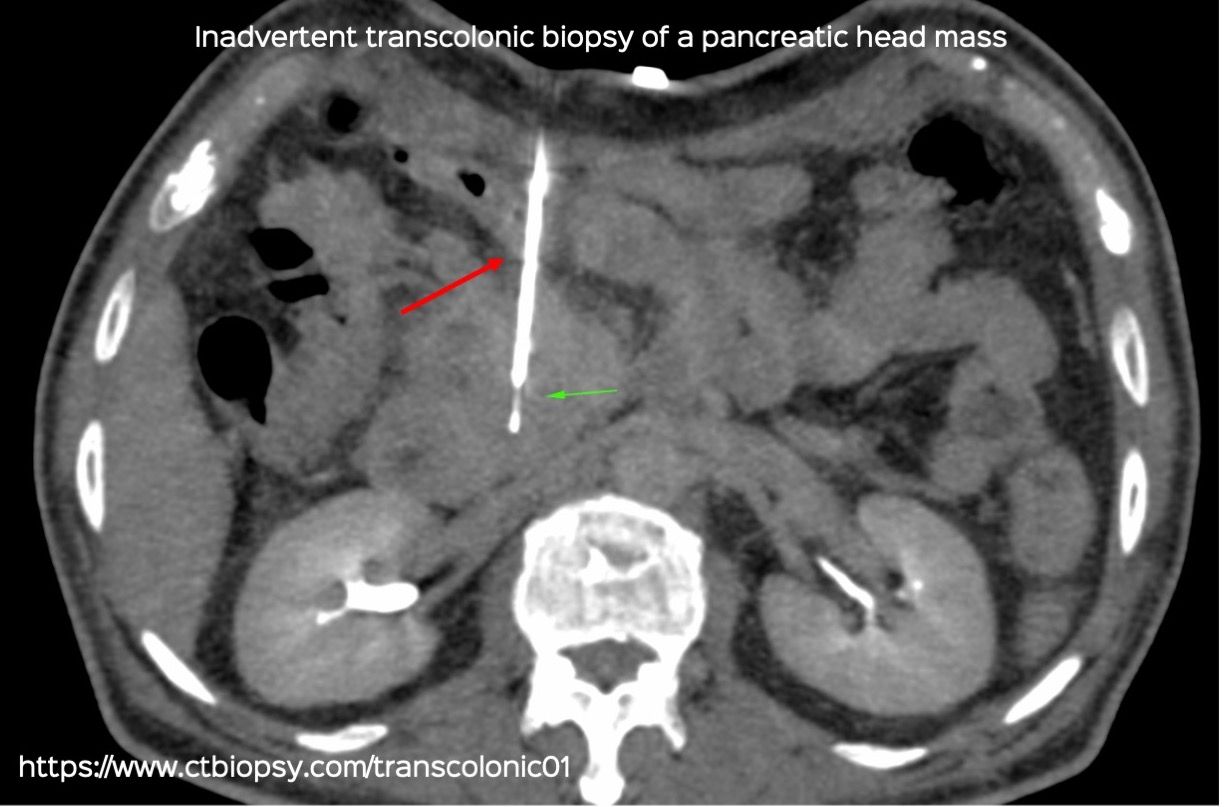

Case 79: Inadvertent Transcolonic Biopsy of a Pancreatic Head Mass